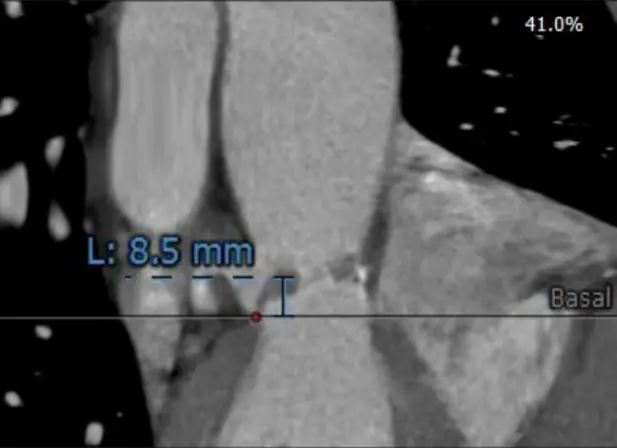

患者男性,70岁,重度钙化型主动脉瓣狭窄,STS评分8.6%,常规外科手术高风险。术前心脏超声提示主动脉瓣严重增厚钙化,峰值流速5.4m/s,平均跨瓣压差82mmHg。CT评估结果显示主动脉瓣重度钙化,瓣环平均直径23.9mm,瓣环面积448.4mm²。左冠脉开口高度8.5mm,右冠脉开口高度12.2mm。该患者左、右冠状动脉开口高度低,左冠瓣叶较长伴钙化,且瓦氏窦较小,窦管交界处高度低,冠状动脉阻塞风险高,手术操作复杂。

左冠瓣叶长度

左冠状动脉高度